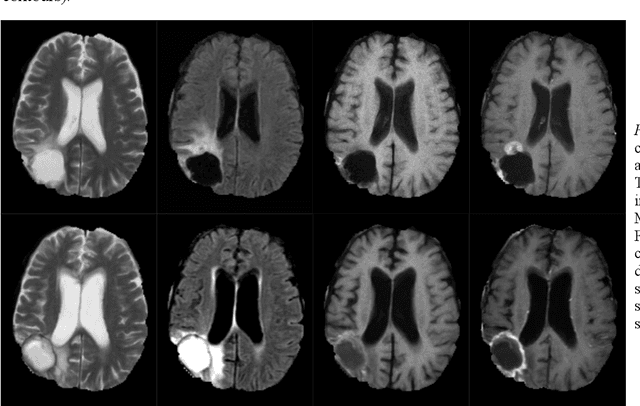

Abstract:In this work, we compare five deep learning solutions to automatically segment the resection cavity in postoperative MRI. The proposed methods are based on the same 3D U-Net architecture. We use a dataset of postoperative MRI volumes, each including four MRI sequences and the ground truth of the corresponding resection cavity. Four solutions are trained with a different MRI sequence. Besides, a method designed with all the available sequences is also presented. Our experiments show that the method trained only with the T1 weighted contrast-enhanced MRI sequence achieves the best results, with a median DICE index of 0.81.